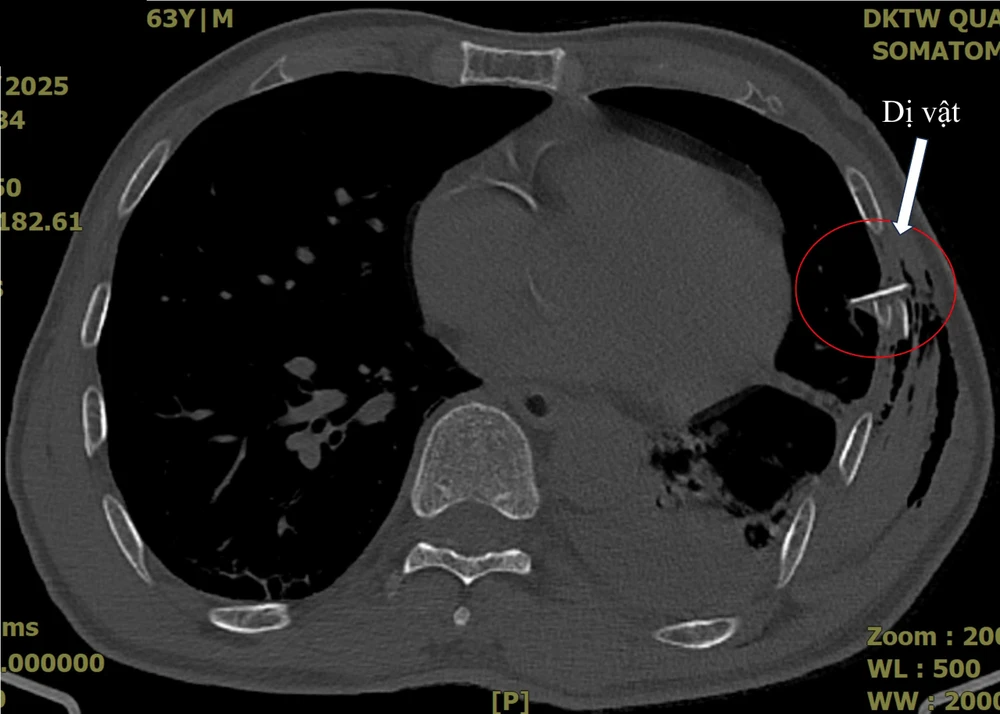

Hình ảnh chụp cắt lớp, bệnh nhân bị xương sườn đâm thủng phổi. Ảnh: BV

Bệnh nhân được chụp cắt lớp ngực và ghi nhận tràn khí, tràn máu màng phổi với hình ảnh mảnh xương sườn đâm vào nhu mô phổi.